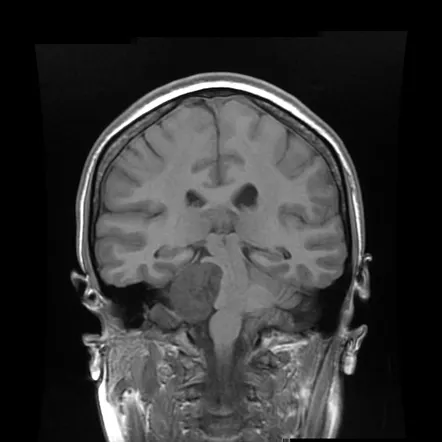

T1 weighted sequences

T1 weighted sequences are part of almost all MRI protocols and are best thought of as the most 'anatomical' of images, resulting in images that most closely approximate the appearances of tissues macroscopically, although even this is a gross simplification.

The dominant signal intensities of different tissues are:

•

fluid (e.g. urine, CSF): low signal intensity (black)

muscle: intermediate signal intensity (grey)

fat: high signal intensity (white)

brain

◦

grey matter: intermediate signal intensity (grey)

white matter: hyperintense compared to grey matter (white-ish)